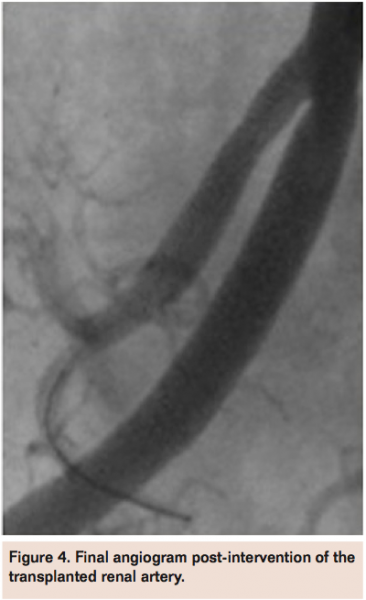

However, it was not until selective right external iliac artery angiogram from the left common femoral artery in the left anterior oblique view was performed that a significant stenosis of the TRA at the anastomosis site was visualized (Figure 2). An 8 Fr MP guide was used to selectively engage the TRA and a guidewire advanced across the lesion into the distal vessel (Figure 3). After predilation with a compliant balloon, an Express 5 mm x 16 mm stent (Boston Scientific) was deployed and post-dilated using a 6 mm x 20 mm balloon with excellent angiographic result and brisk flow (Figure 4).

The patient tolerated the procedure well without any complications and by the following day, she was producing 75-100 cc of urine/H. Two weeks post-procedure, her renal function had significantly improved with creatinine of 1.4 off HD. More recently at 1-year follow-up, the patient was clinically stable off HD and with baseline creatinine of 0.9.